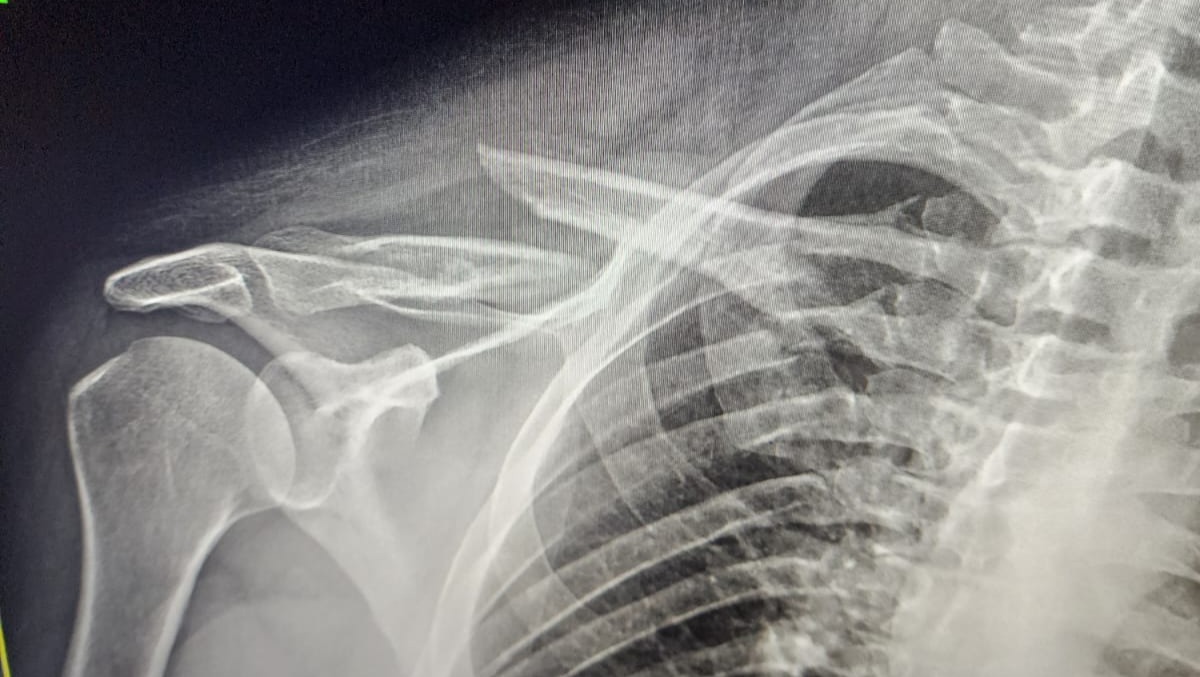

Had a follow up visit for his shoulder. Upon reviewing the images, we were able to see how the fracture is. He has a mid shift clavicle fracture. His shoulder is currently shifted down around 2 inches. Next step is shoulder surgery.

On May 30th, 2023 he was involved in serious motorcycle accident and had to be rushed to Memorial Regional Hospital Trauma. As he was turning, a vehicle cut him off, he had to slam his breaks to avoid hitting that vehicle and tried to maintain control of his bike. While trying to maintain control, the tired locked and flung him off the bike. Unfortunately, he was not wearing a helmet and suffered multiple brain bleeds which will heel over time but are causing a lot of pain. He had a piece of asphault stuck in his ear which required stitches. Also had 3 fractures on his collar bone.